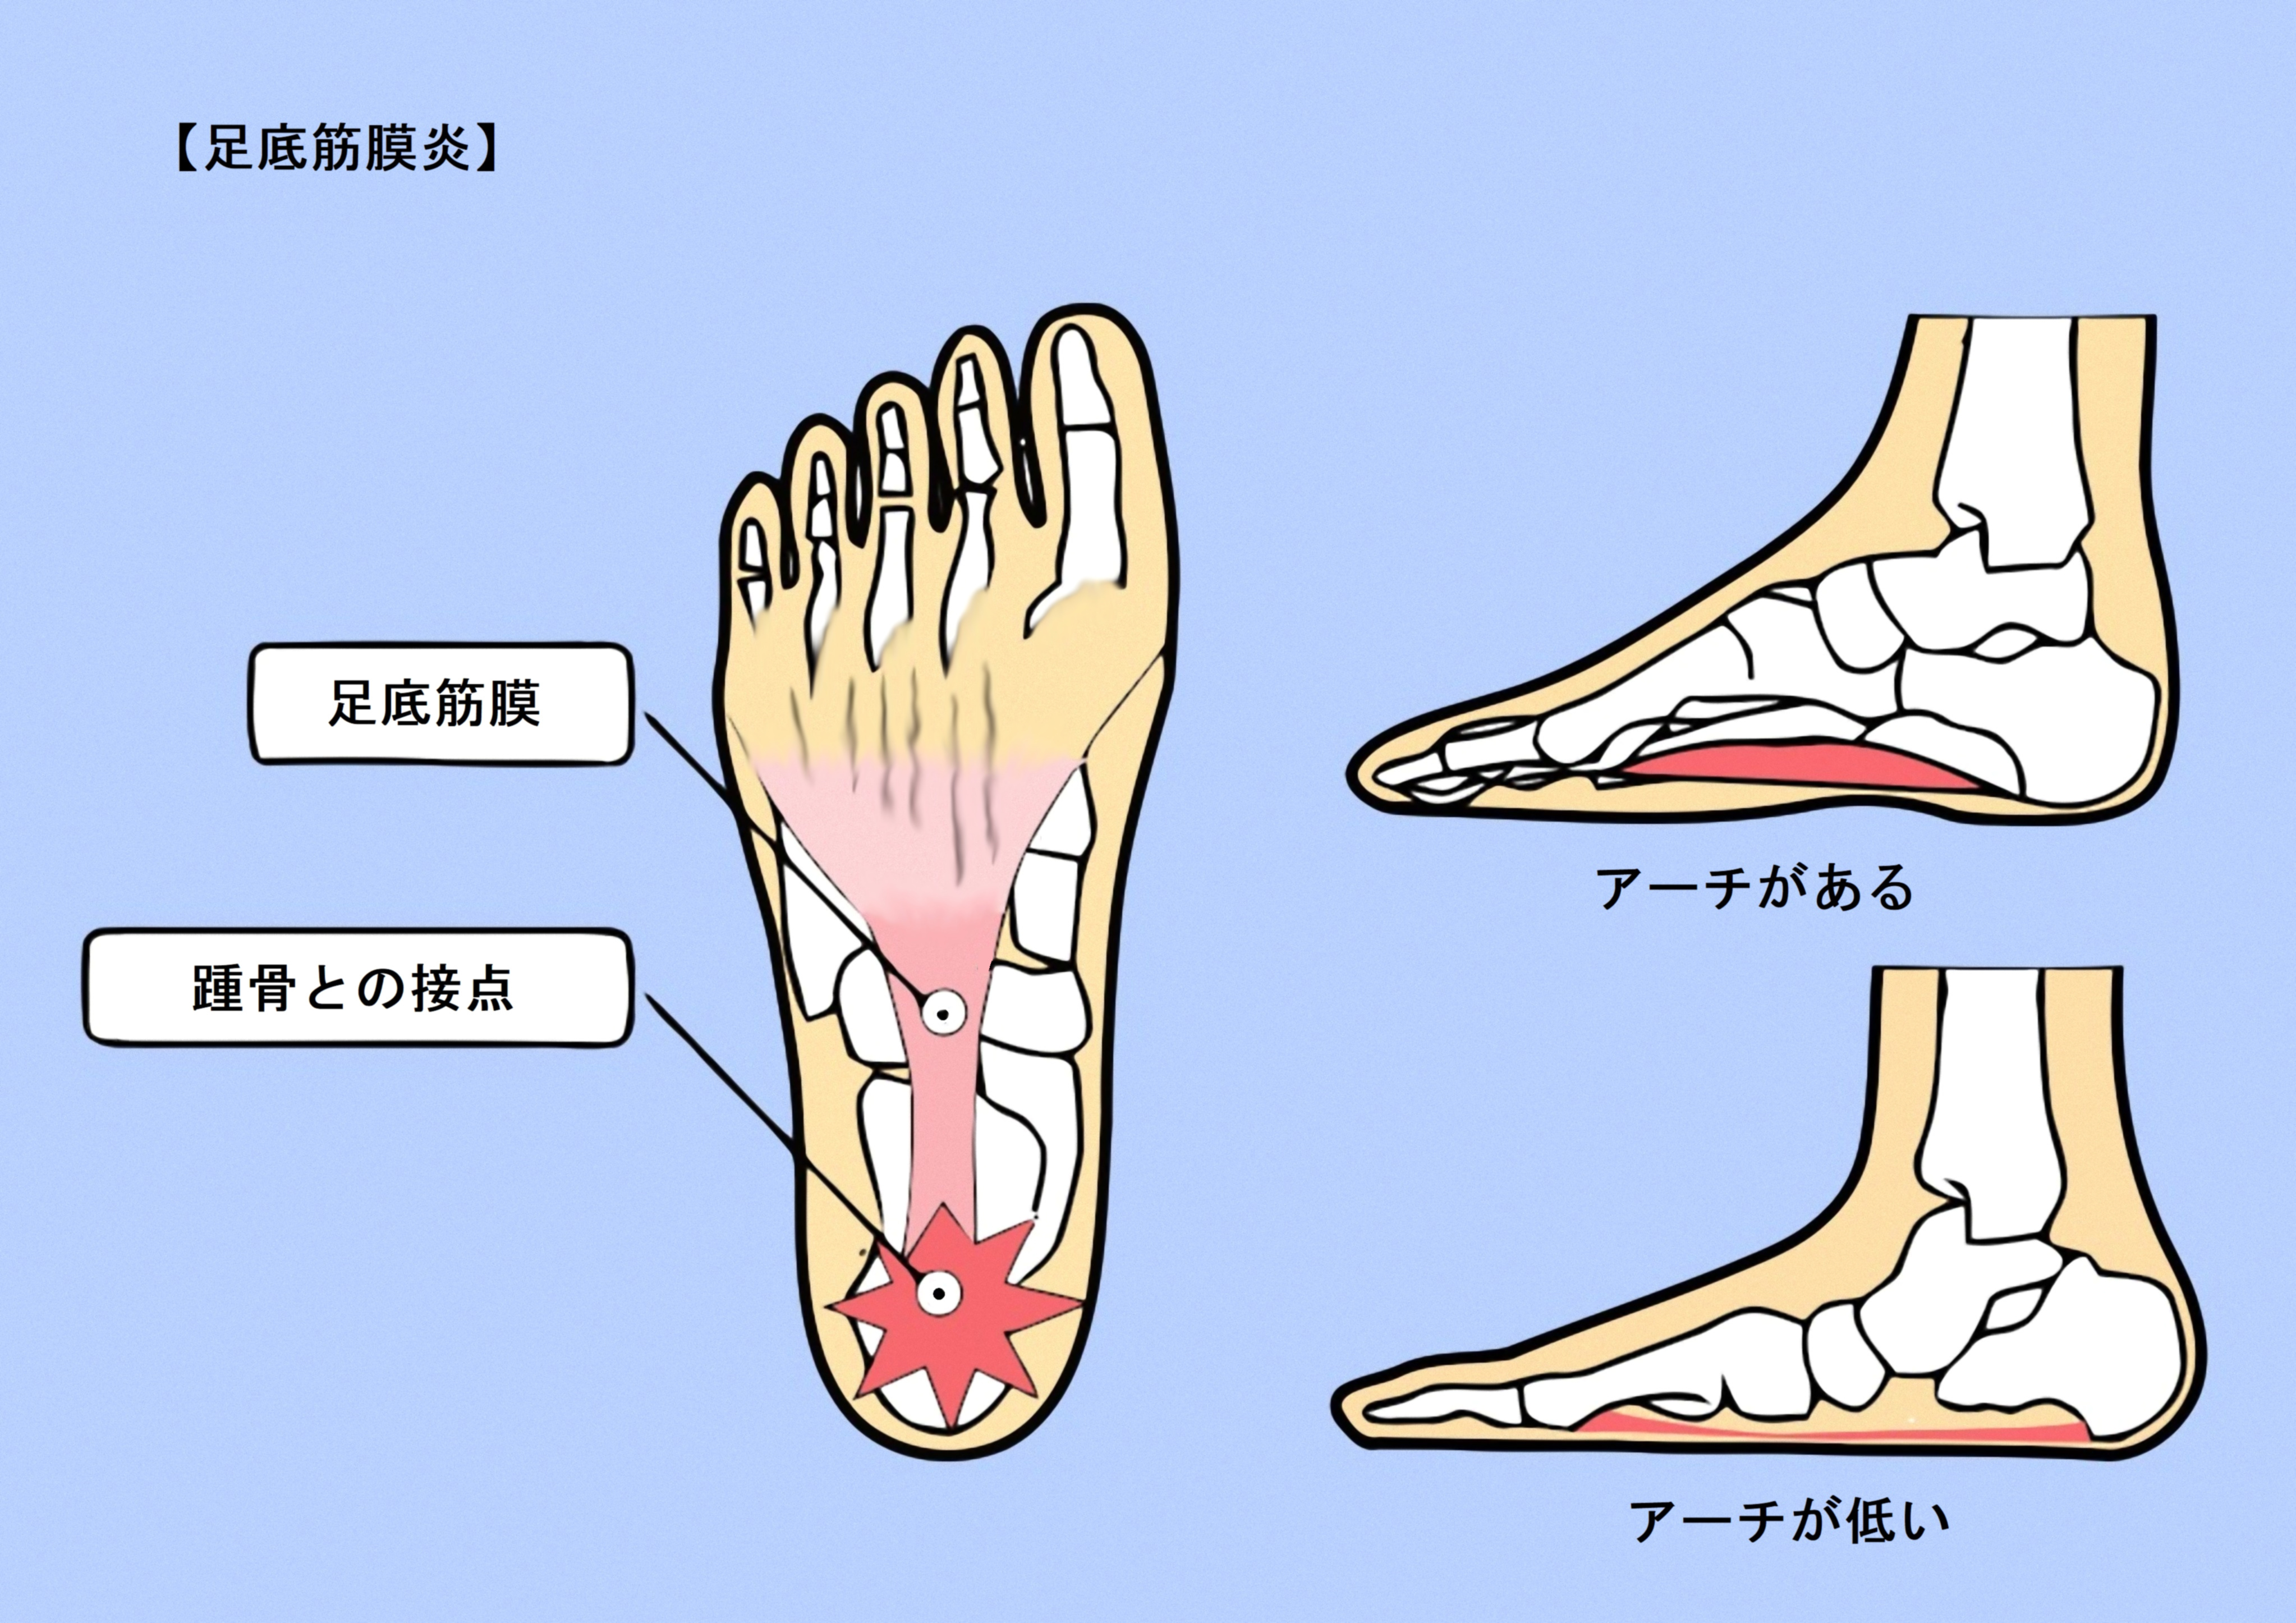

足底筋膜炎は、かかとや足の痛みの一般的な原因です。幸いなことに、自宅でできるストレッチや足のマッサージは痛みを和らげ、症状の慢性化を防ぐのに役立つ可能性があります。

「ランナー、立ち仕事が多い人、扁平足や高いアーチの人は、足底筋膜炎になりやすいです。正しい歩き方を心がけ、筋肉が硬くならないように運動やストレッチをする必要があります」と彼女はアドバイスします。